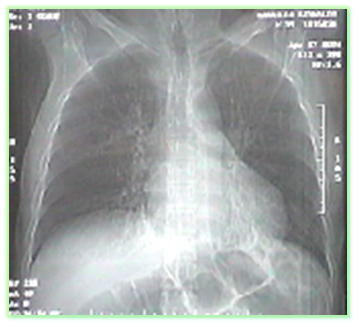

TOMOGRAFIA COMPUTARIZADA DE TORAX SIMPLE .

INDICACIONES.

TRAUMA DE TORAX

POSICION Y ORIENTACION DEL PACIENTE PARA LA REALIZACION DEL EXAMEN

El paciente debe ubicarse en la mesa de exploración en decúbito supino con la cabeza hacia el gantry y con los brazos elevados, en algunas ocasiones se utilizan inmovilizaciones en caso de que el paciente sea discapacitado o no colabora durante el proceso del examen, para que las imágenes diagnosticas no queden movidas cuando aparezca en el monitor de la consola

EVIDENCIAS DE IMAGENES DIAGNOSTICAS DE UNA TOMOGRAFIA DE UN TORAX SIMPLE

VENTANA PULMONAR